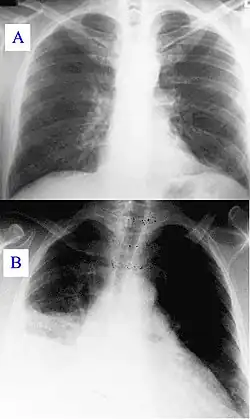

![]() | |

| Immunohistochemical detection of C. burnetii in resected cardiac valve of a 60-year-old man with Q fever endocarditis, Cayenne, French Guiana: Monoclonal antibodies against C. burnetii and hematoxylin were used for staining; original magnification is ×50. | |